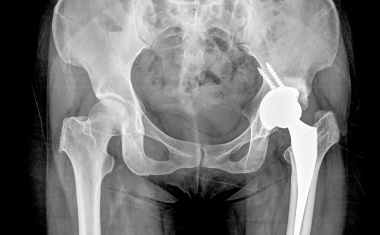

Sich endlich wieder ohne Schmerzen bewegen können - Bei Gelenkverschleiß schafft das Endoprothetikzentrum des Hospitals zum Heiligen Geist Abhilfe.